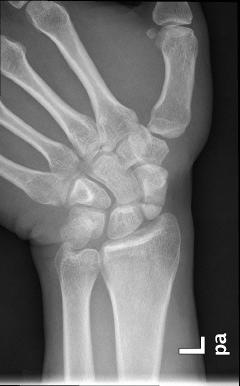

Το σκαφοειδές ανήκει στα μικρά οστά του καρπού και είναι αυτό που υφίσταται κάταγμα συχνότερα. Συνήθως συμβαίνει στις ηλικίες 20 - 40 ετών. Οσο κεντρικότερα (προς τον αγκώνα) είναι το κάταγμα τόσο δυσμενέστερη είναι η πρόγνωση για την πώρωσή του («κόλλημα» του κατάγματος).

Τα περισσότερα κατάγματα σκαφοειδούς μπορεί να αντιμετωπιστούν επιτυχώς χωρίς χειρουργική επέμβαση. Αυτό όμως συνεπάγεται γύψινη ακινητοποίηση από 8 εβδομάδες έως και 6 μήνες. Γι’ αυτό η τρέχουσα τάση είναι να χειρουργούνται, εκτός εάν συντρέχουν λόγοι που αποτρέπουν αυτή την απόφαση. Χρησιμοποείται ειδικά σχεδιασμένες βίδες ή βελόνες. Με τον τρόπο αυτό αποφεύγεται η χρήση γύψου, ο ασθενής επιστρέφει ταχύτερα στην εργασία του και οι επιπλοκές περιορίζονται σημαντικά.

Τονίζεται το θέμα της αιμάτωσης του σκαφοειδούς, διότι εύκολα διαταράσσεται σε κατάγματα, με αποτέλεσμα την εμφάνιση επιπλοκών, όπως άσηπτη νέκρωση του κεντρικού τμήματος ή καθυστερημένη πώρωση κσι ψευδάρθρωση (δηλαδή μή πώρωση). Αυτές οι επιλοκές αντιμετωπίζονται χειρουργικώς με χρήση οστικών μοσχευμάτων σε συνδυασμό με σύνθετες τεχνικές (βλ σχετικό κεφάλαιο).